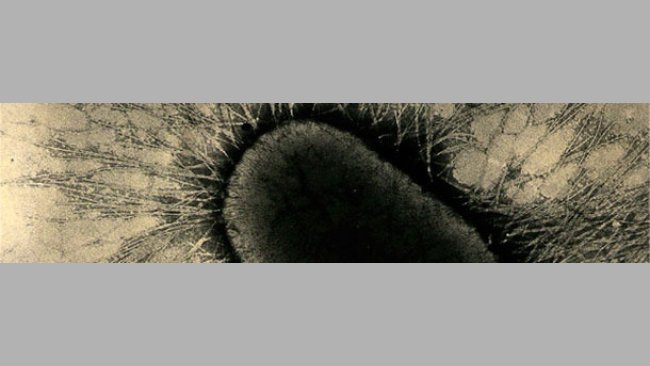

Figura 1. Cultivo puro de E. coli hemolítica en agar sangre. La zona clara alrededor de cada colonia bacteriana indica hemólisis (descomposición de la sangre en placa de agar). Fuente: Universidad Estatal de Iowa, Laboratorio de Diagnóstico Veterinario, Sección de Bacteriología.